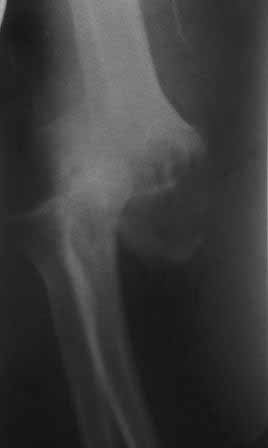

Вывих предплечья

Пациент 45 л. Обратился к нашему доктору с жалобами на боли и ограничение движений в правом локтевом суставе, под углом 140гр., движения качательные, болезненные.

Травму получил 7 месяцев назад. Д-з " застарелый задненаружный вывих предплечья"

В предварительном плане артродез в функционально выгодном положении, или резекция сустава - хоть какие-то будут движения. Может быть, метод Илизарова ?